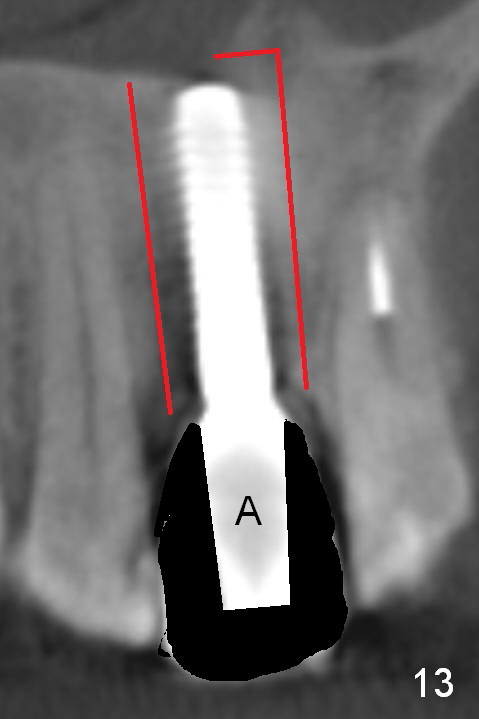

Fig.10 is a sagittal section of the implant (arrowheads: nasal floor). It is apparent that there is enough space (Fig.11,12 (PA)) for osteotomy (Fig.13 red lines: A: angled Titanium abutment). With the palatal mucoperiosteal flap attached the implant/bone segment, it is moved apically (Fig.14). Coronally the coronal portion is repositioned palatally while the apical portion buccally (Fig.15 arrows). Is the segment stable?